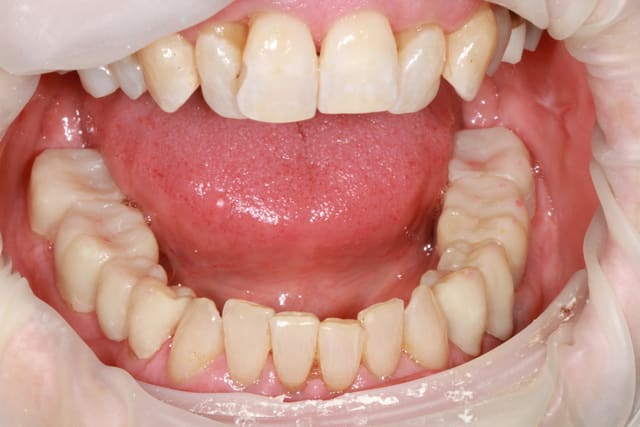

patiente 62 ans région Parisienne, appelle pour un avis, son praticien, paro, imlpanto etc... lui dit que sa paro n'a plus besoin de soin et propose pour les 6 antérieurs (j'ai le devis sous les yeux) 6 Inlay Core et 6 CCM...

Les panos sont du départ, les photos sont après un nettoyage ...profond et soins.

le problème de départ de cette patiente est paro...et bien sur l'ortho est une bonne idée, mais je ne pense pas que l'ortho permette de rétablir une DV correcte.

donc dans un premier temps détartrage, détartrage, détartrage Wax up, ....surfaçage couronne , amalgame à la benne taille des postérieurs inférieure et pose de provisoires pour valider la nouvelle DV.